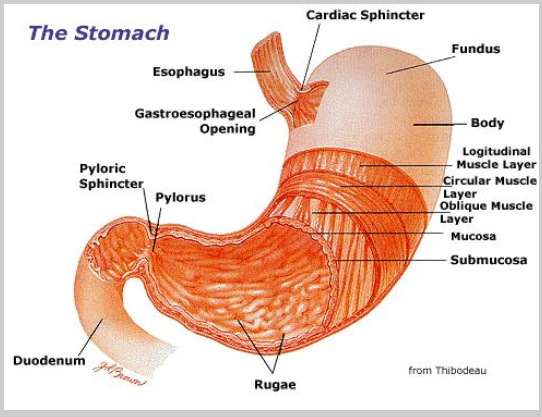

Digestive Disorders & Gastrointestinal Diseases | Cleveland Clinic

Functional disorders are those in which the gastrointestinal (GI) tract looks normal but doesn’t work properly. They are the most common problems affecting the GI tract (including the colon and rectum). Constipation and irritable bowel syndrome (IBS) are two common examples.

Digestive Disorders & Gastrointestinal Diseases

Digestive Discussion orders per HCL agent Hillary CL

Role of Hydrochloric Acid in the Stomach | LIVESTRONG.COM

Apr 11, 2011 – Hydrochloric acid, also called HCl, is a clear, highly corrosive liquid. HCl is one of the many chemicals released in our stomach when we eat a …